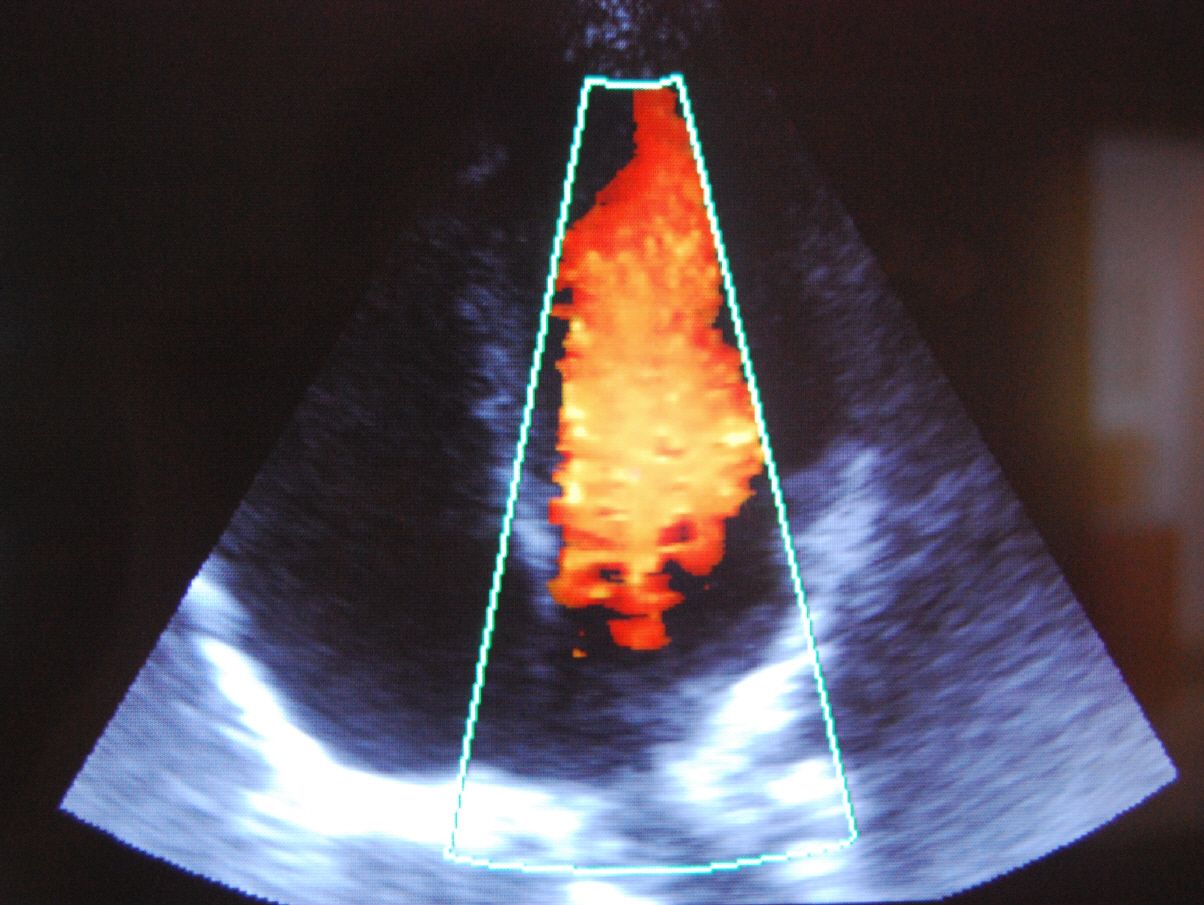

Sie sind hier: Gemeinschaftspraxis Benthake/Othman/Önder » Leistungen » tech. Untersuchungen » Echokardiografie